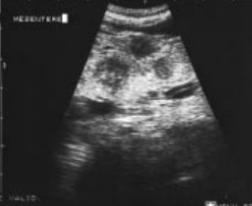

Image echographique de la tuberculose

ileo-caecale est : Image epaissisement hypoechogene de la

paroi du colon et image de lymphadenopathie .

Aspect TDM du tuberculose ileocaecale est : Epaissisement

circumferentiel de la paroi ileum et caecum . Asymetrique

epaissisement de la valve ileocaecale .Mesenteric

lymphadenopathie et tuberculose pulmonaire est le plus

souvent .